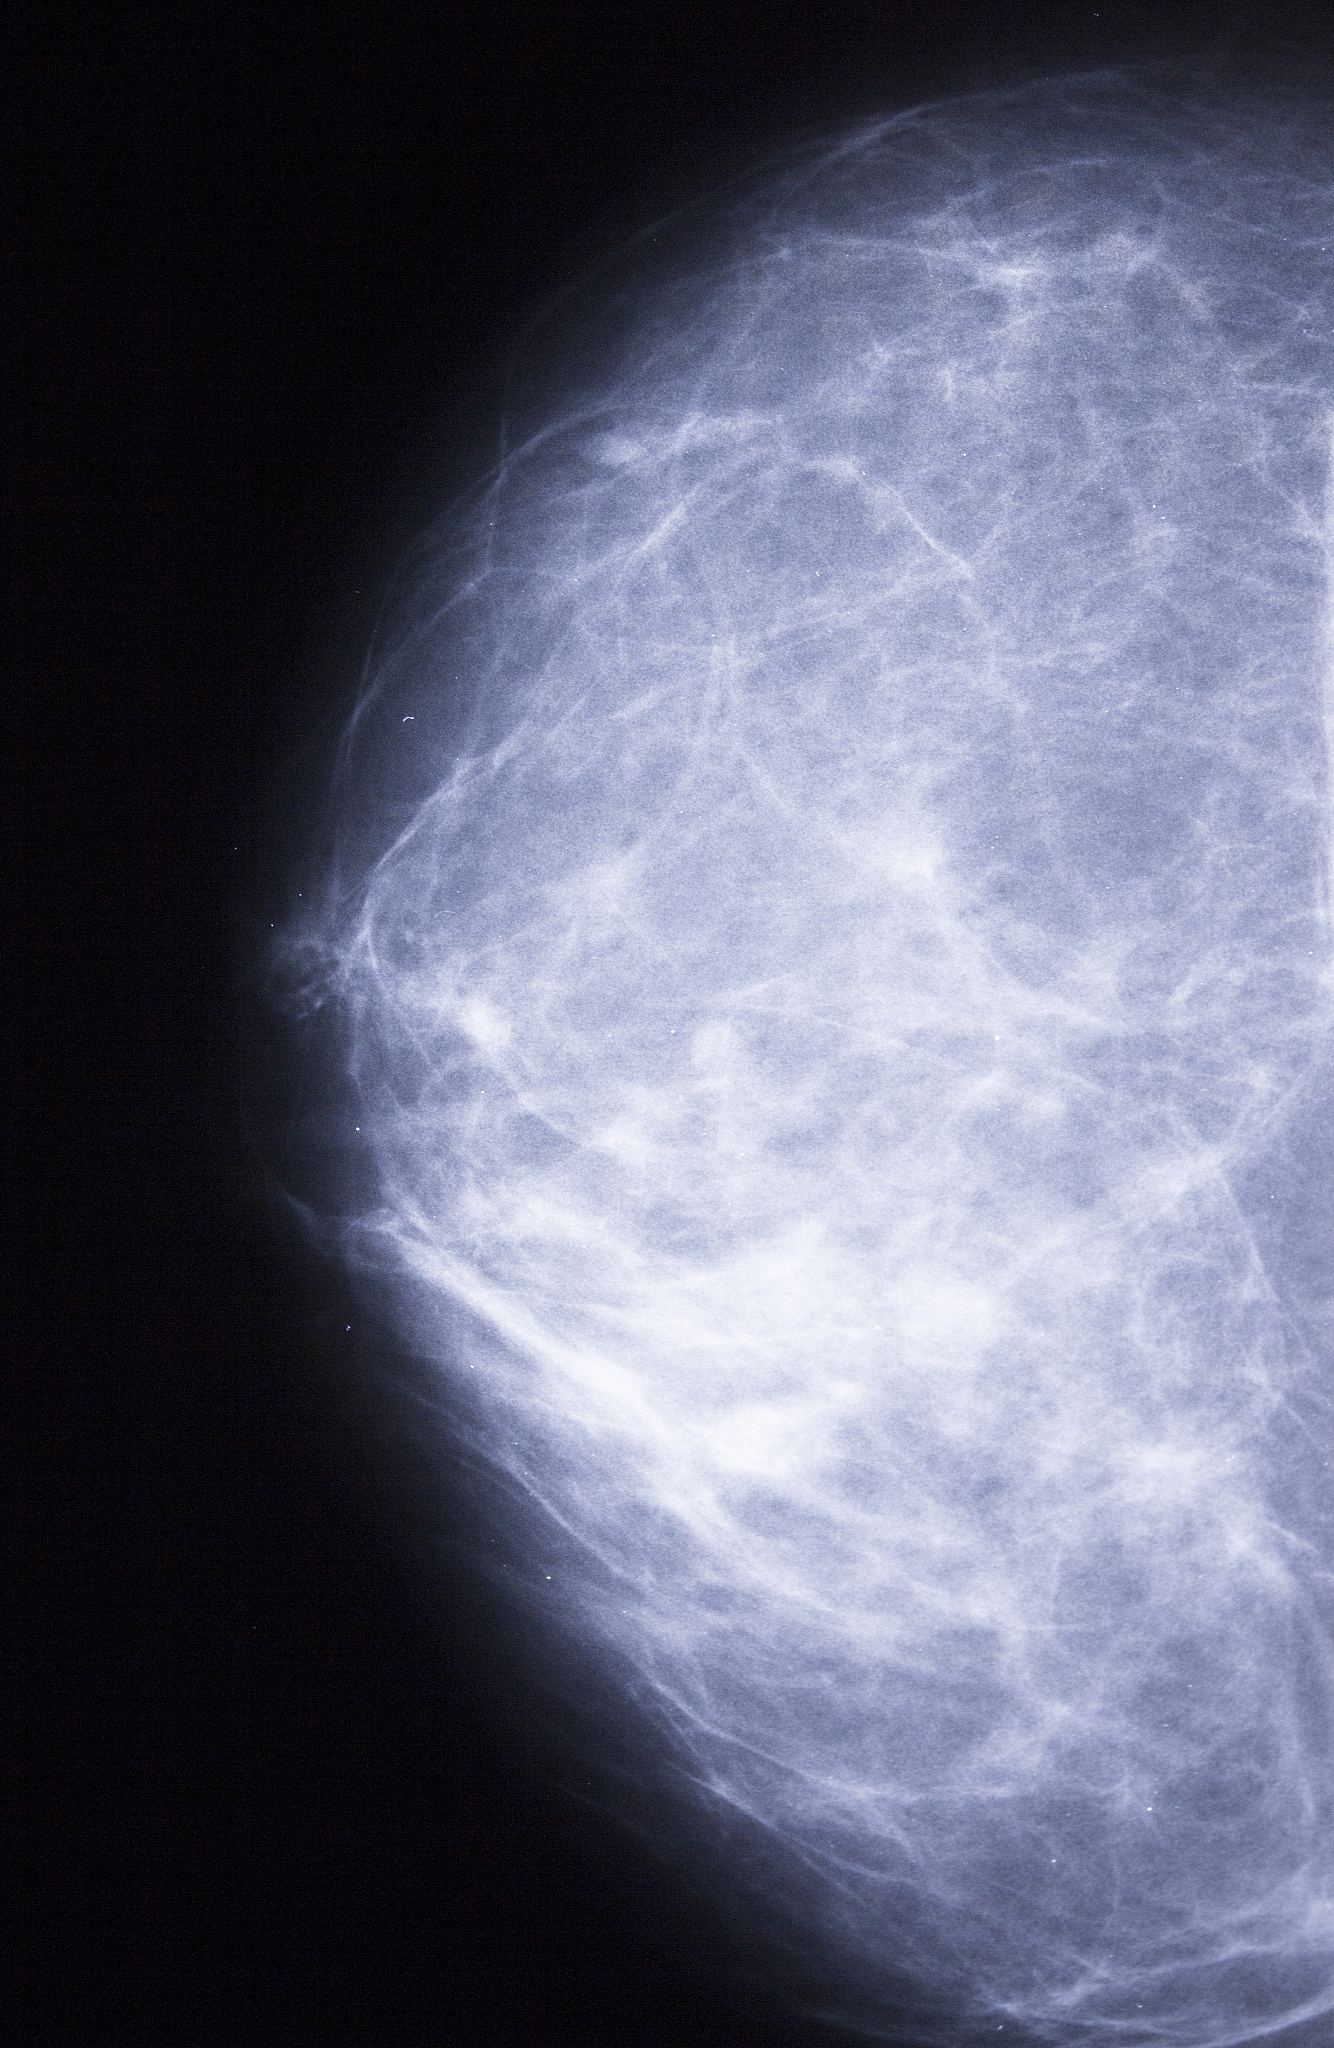

乳腺肿瘤的分类与分割是指利用医学影像技术,例如X光、超声、磁共振等,对乳腺肿瘤进行识别、分类和定位的过程。这项技术在现代乳腺癌诊疗中发挥着越来越重要的作用,其优势主要体现在以下几个方面:

1. 精准诊断,辅助决策: 乳腺肿瘤的分类与分割可以帮助医生更准确地诊断乳腺肿瘤,确定肿瘤的类型(如良性或恶性)、大小、形态、位置等关键信息,为制定最佳治疗方案提供可靠依据。